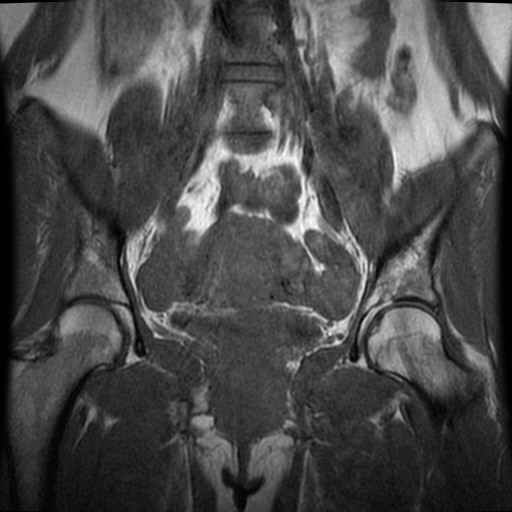

bekken